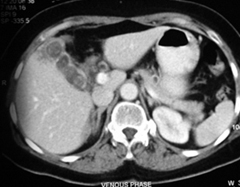

Diagnosis is usually confirmed on Sonography & Computerized tomography (CT) scan. Additional blood test is performed to access the Liver function.